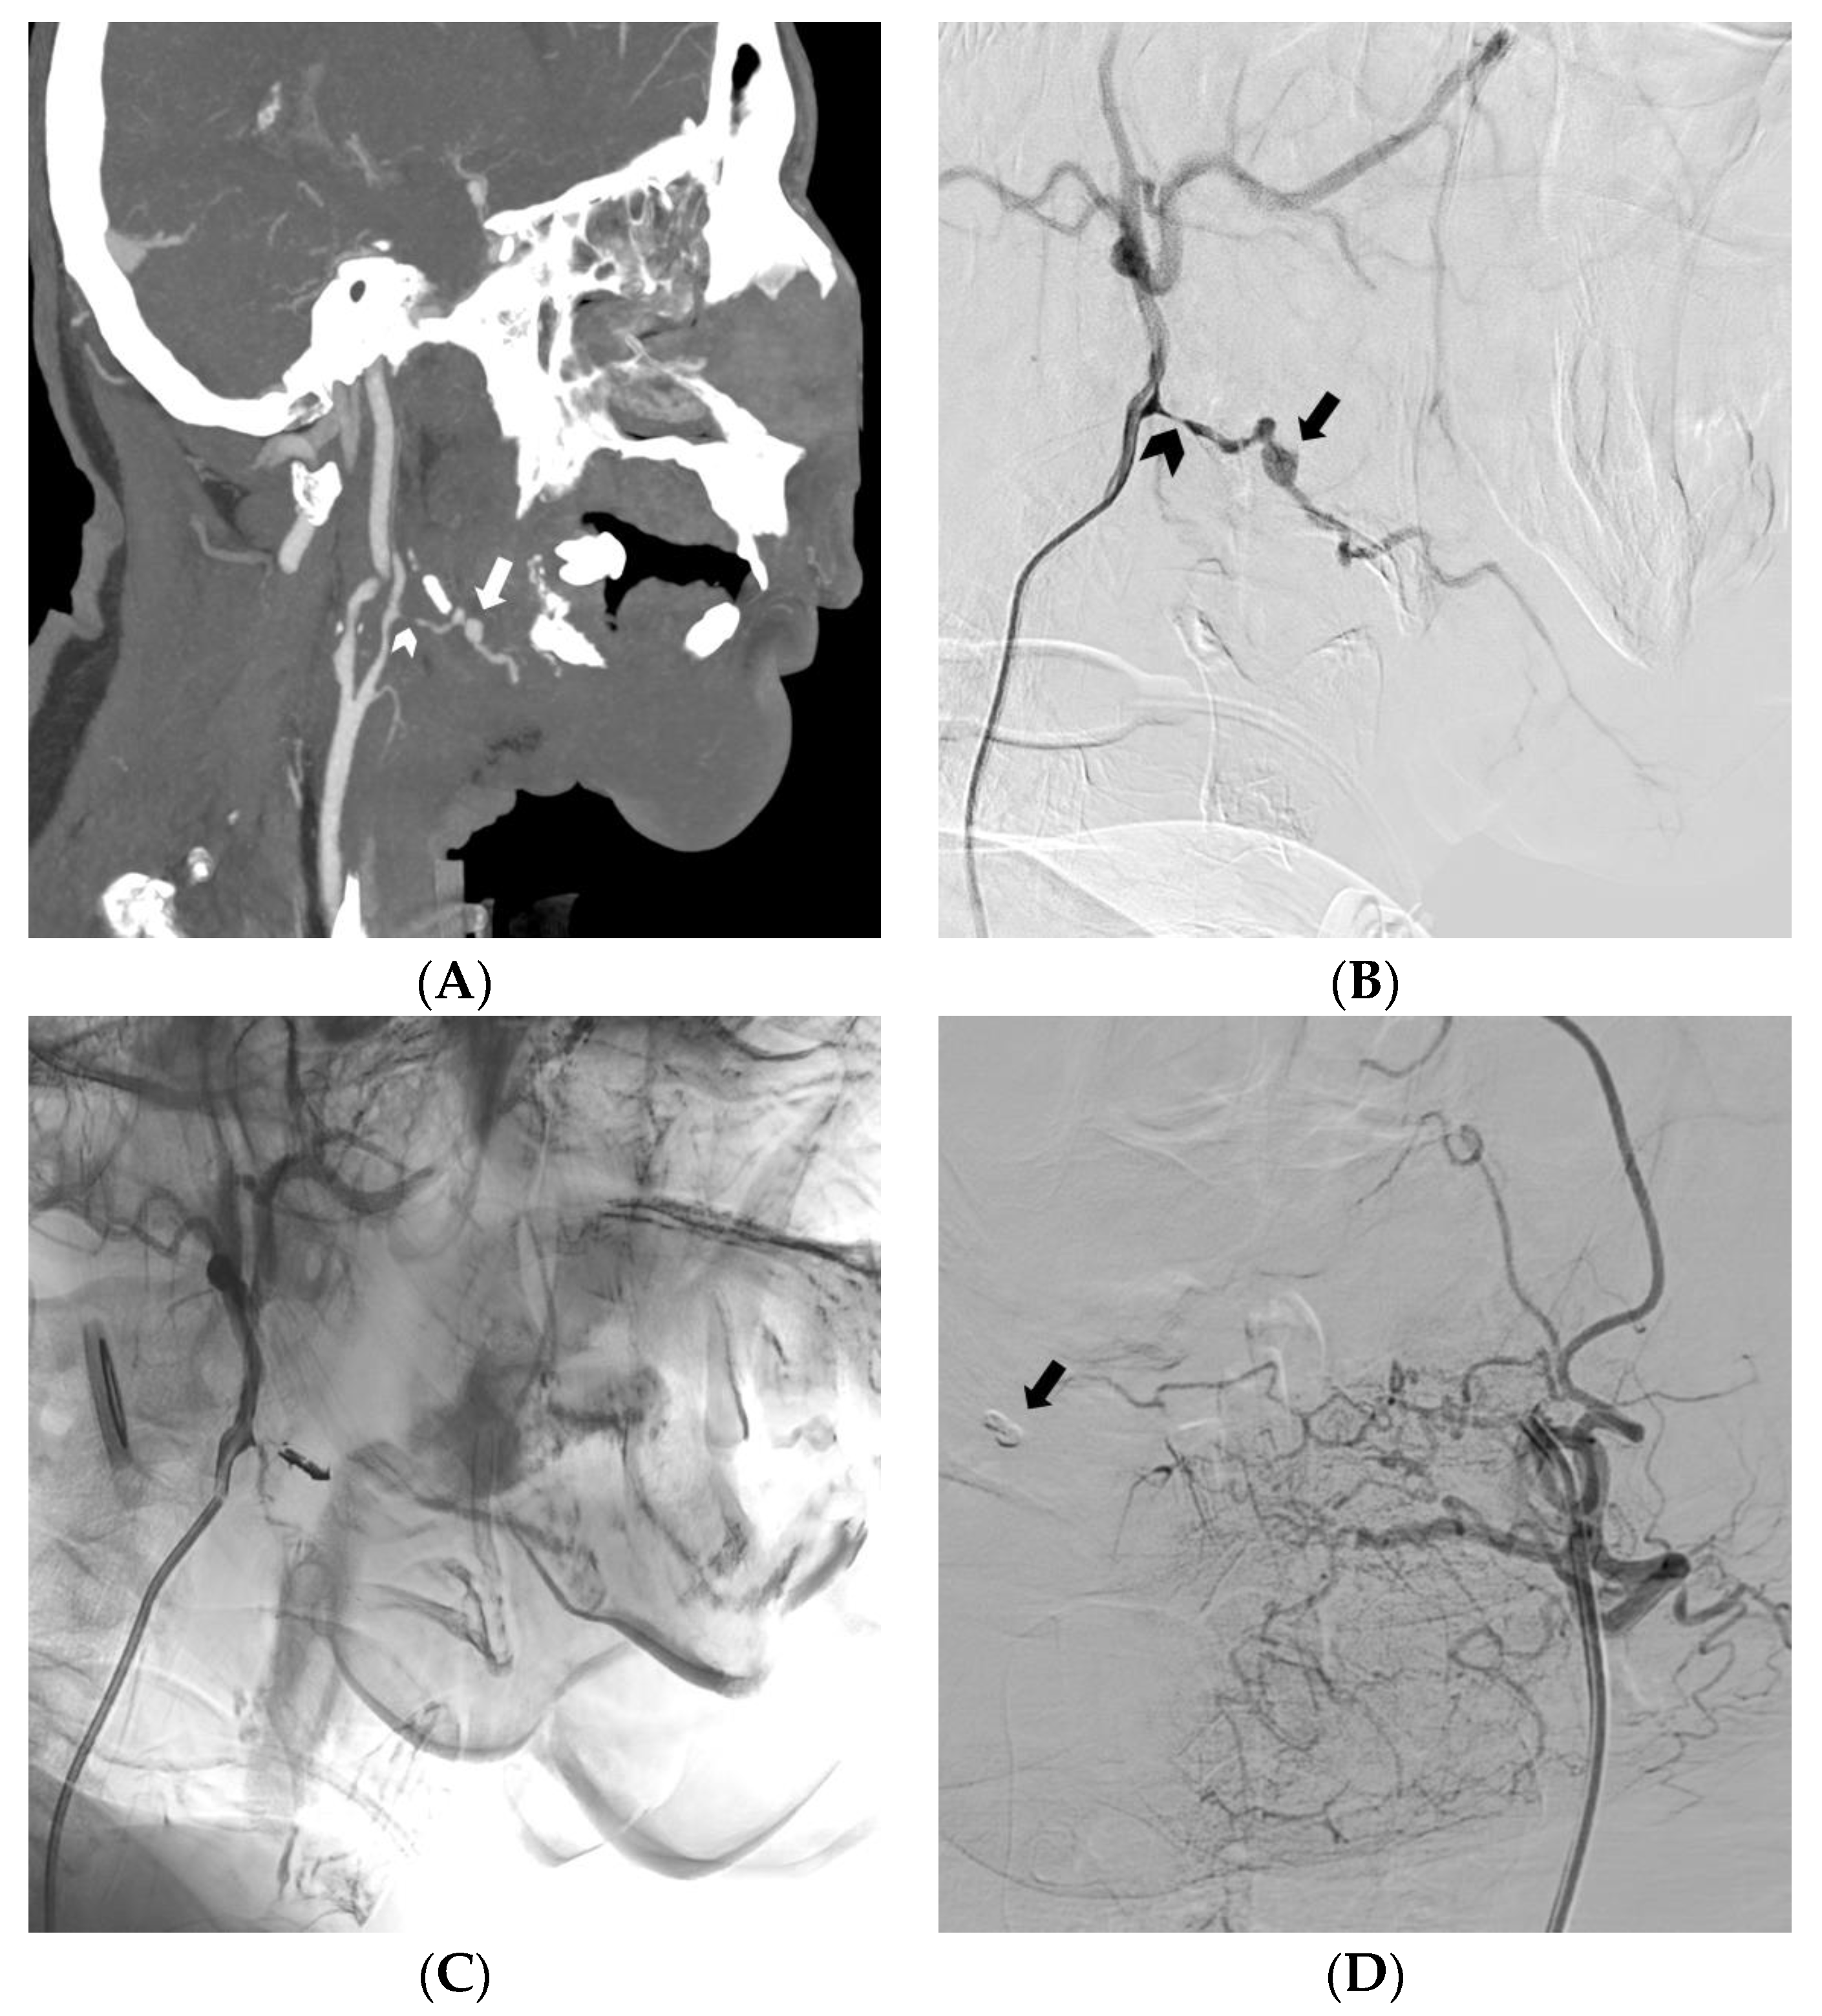

- Kim, J.; Park, S.K.; Chung, J. Role of Transarterial Embolization in the Treatment of Life-Threatening Hemorrhage in Patients With Maxillofacial Injury. Korean J. Neurotrauma 2022, 18, 178. [Google Scholar] [CrossRef]

- Müller-Wille, R.; Heiss, P.; Herold, T.; Jung, E.M.; Schreyer, A.G.; Hamer, O.W.; Rennert, J.; Hoffstetter, P.; Stroszczynski, C.; Zorger, N. Endovascular Treatment of Acute Arterial Hemorrhage in Trauma Patients Using Ethylene Vinyl Alcohol Copolymer (Onyx). Cardiovasc. Interv. Radiol. 2011, 35, 65–75. [Google Scholar] [CrossRef]